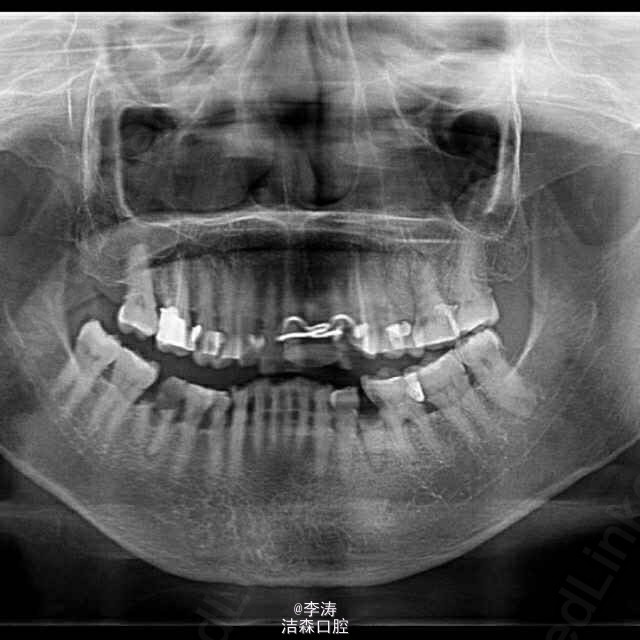

多颗牙牙痛根管治疗1例

这是接诊的最难的一例病例,患者65岁女性,主诉牙齿疼痛,检查基本上全口邻面深龋,治疗完左边,右边又痛,结果是全口多数牙都被根管治疗,治疗完准备不做冠,又被咬崩,结果又不得不将根管治疗的牙全做冠。